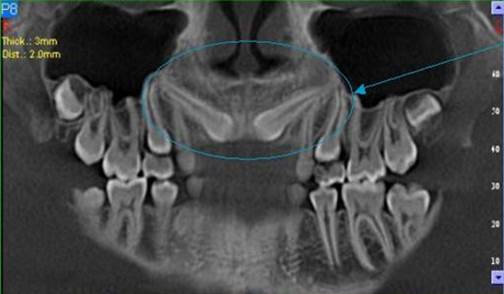

3D DVT - NewTom

Je speciální zubní digitální tříprostorový tomograf (3D), který umožňuje na základě jediného

snímkování vytvořit všechny typy RTG zobrazení, které jsou pro lékaře potřebné. Díky používané technologii tzv. „kuželového paprsku“ a speciálním senzorům je

výrazně zmenšená dávka záření - o více jak 80% proti klasickému CT vyšetření. To je významné zejména u dětí. Pomocí tohoto přístroje je možné zjisti skutečnou situaci v čelistních kostech pacienta tedy množství kosti - můžeme změřit skutečnou šířku i výšku kosti, i kvalitu kosti (hustotu) v místě uvažované implantace. 3D (tříprostorové) zobrazení umožňuje zvýšit prostorovou představu operatéra ještě před vlastní operací a zároveň pacientovi lépe objasnit a ukázat oblast plánovaného zavedení implantátu.

Vyšetření pomocí tohoto přístroje používáme i ve stomatochirurgii (zlomeniny čelistí, zuby moudrosti, cysty, onemocnění čelistního kloubu), ortodoncii (retinované zuby, nadpočetné zuby), parodontologii atd.